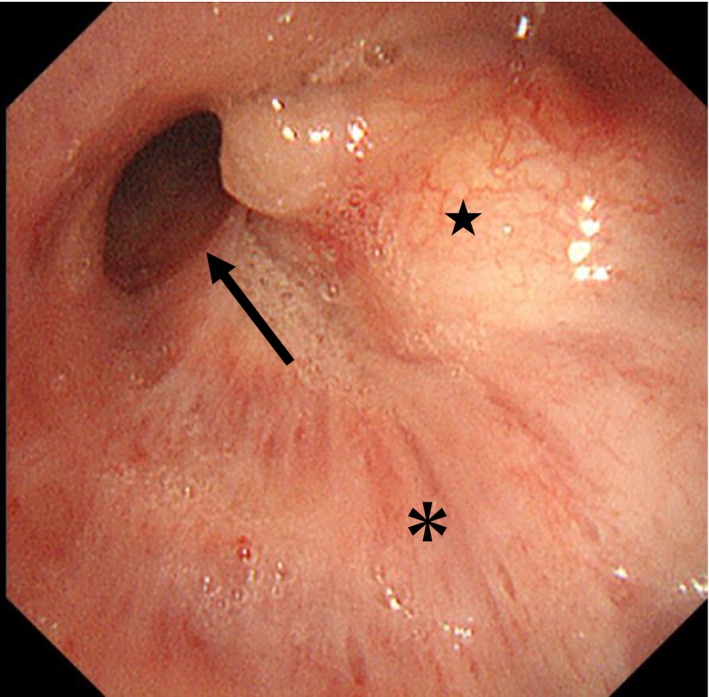

Various endobronchial therapies, as well as complete surgical resection, have recently been reported. Among them, microwave coagulation is a promising endobronchial therapy for a wide range of neoplasms due to its high efficacy and safety. Meanwhile, endobronchial lipoma is a benign tumour that is rarely observed in the lungs. To our knowledge, the efficacy of microwave coagulation has not been reported in the treatment of endobronchial lipoma. Here, we report the effectiveness of endoscopic microwave coagulation therapy in safely resolving atelectasis and cough caused by endobronchial lipoma. Surgical resection was deemed to be unsuitable in this case due to the likelihood of extensive surgery such as right lower lobectomy being required, and comorbidities including poorly controlled diabetes mellitus. There was an elevated risk of perioperative complications. This report presents a new, effective, and minimally invasive treatment option for endobronchial lipoma in endoscopic microwave coagulation to relieve atelectasis.